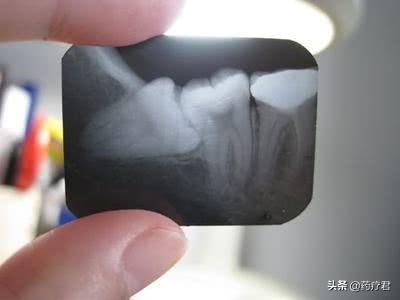

毕竟是身体自己长出的东西,即便没有用,还是能留尽可能留的吧。尤其是那些长得还算周正,没有发过炎,与周边牙齿的关系还算融洽的智齿,是没有必要拔除的。值得说明的是,有时候,智齿还能作为“候补队员”来救场,那就是第二磨牙已缺失或因病损无法保留,并且这时的智齿又恰哈近中倾斜角度不超过45°,就可以保留作为修复(镶牙)的基牙,避免游离端缺失。

如果智齿出现了龋坏,或者占据了正常牙齿的生长空间,或者经常发炎等情况时,就不要犹豫早拔除早受益。